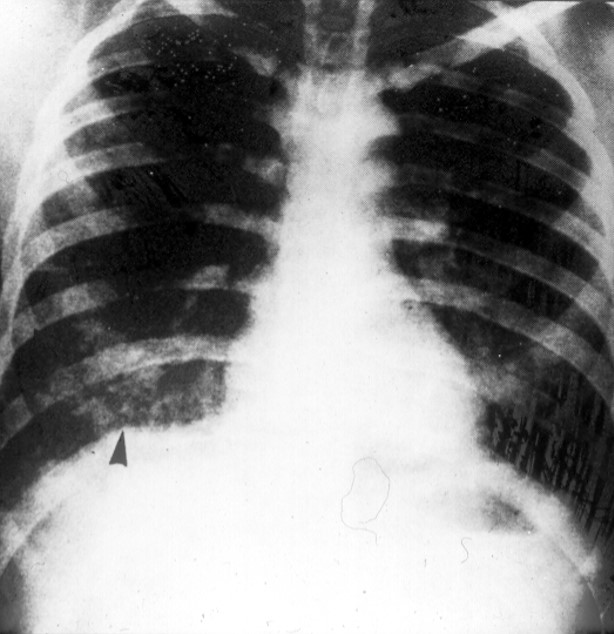

Panel C.

Acute S. mansoni infection. Left image: Cercadial dermatitis ("Swimmer's itch"). This dermatitis appears ˜15 days after swimming or wading in snail-infested fresh water lakes or ponds. Right image: Pulmonary involvement in acute S. mansoni infection. The arrow points to clusters of periovular granulomas giving a "cotton candy"- like appearance .